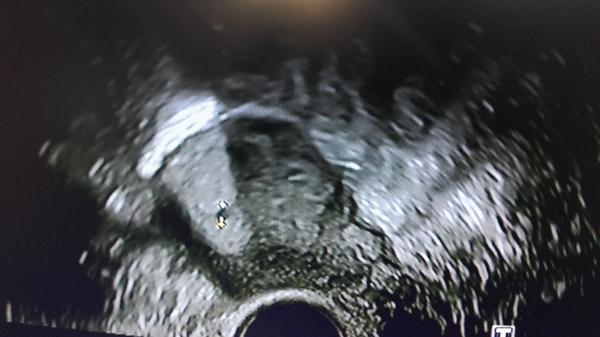

Těhotenský test. Dávám fotku. Co myslíte?

Tak nevim ... ☹ Dávám fotku, skuste posoudit...

@lenulinka10 tak jsem doma. Pan primář mi to potvrdil a objednal mě za 14 dní že to bude líp vidět a že už uvidíme i srdíčko. Tak mám strašnou radost

@lenulinka10 je to krásný pocit vidět tu tečku a věřit že to dobře dopadne. Dostala sem utrogestan a prednison. Tak to bude určitě v poradku